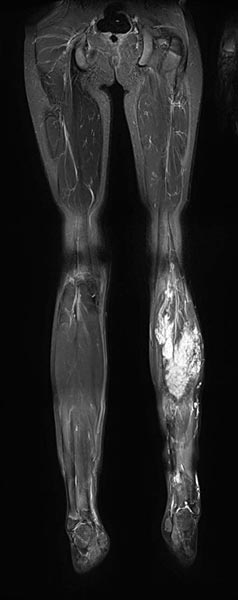

In T2-weighted, fat-suppressed coronal MRI, fibro-adipose vascular anomaly (FAVA) is visible as a hyperintense lesion in the left gastrocnemic muscle.